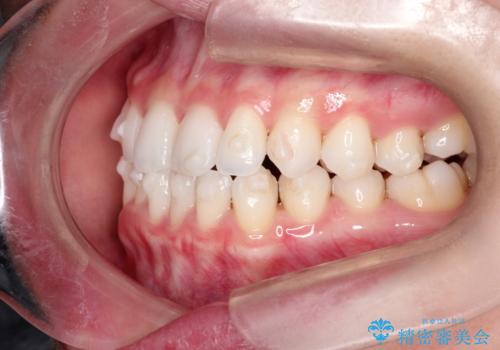

【インビザライン】前歯の凸凹をマウスピース矯正でなおしたい

- 前歯の凸凹を主訴に来院されました。

上の前歯は翼状捻転と呼ばれる状態でしたが、奥歯の遠心移動を行うことで配列スペースを確保することで綺麗に歯を並べることができました、

途中でインビザラインの使用時間が短くなってしまったため期間が予定より少し伸びましたが、1年半で満足いく結果となり患者様に喜んでいただけました。

下顎骨が右側に偏位していることにより下顎前歯の真ん中はずれています。